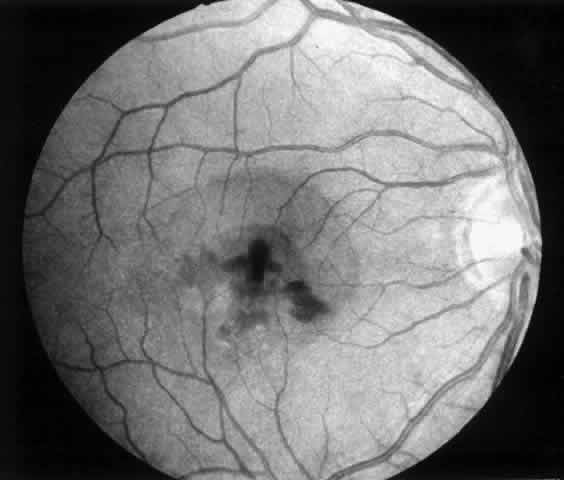

In January 1991, Thomas and Kaplan14 reported an alternative approach to subfoveal neovascularization in POHS. Instead of a large flap retinotomy, their technique employed a small retinal hole through which instruments were introduced into the subretinal space. The neovascular membrane was dislodged, grasped with forceps, and extracted through the slightly enlarged retinotomy. An air-fluid exchange was followed by endolaser burns around the retinotomy and short-term tamponade with sulfur hexafluoride gas. In the first two POHS cases, visual acuity improved dramatically (from 20/400 [6/120] to 20/20 [6/6] in one case and 20/400 [6/120] to 20/40 [6/12] in the second). These early encouraging results prompted refinement of the instrumentation and surgical technique and their application in a wider variety of cases.15